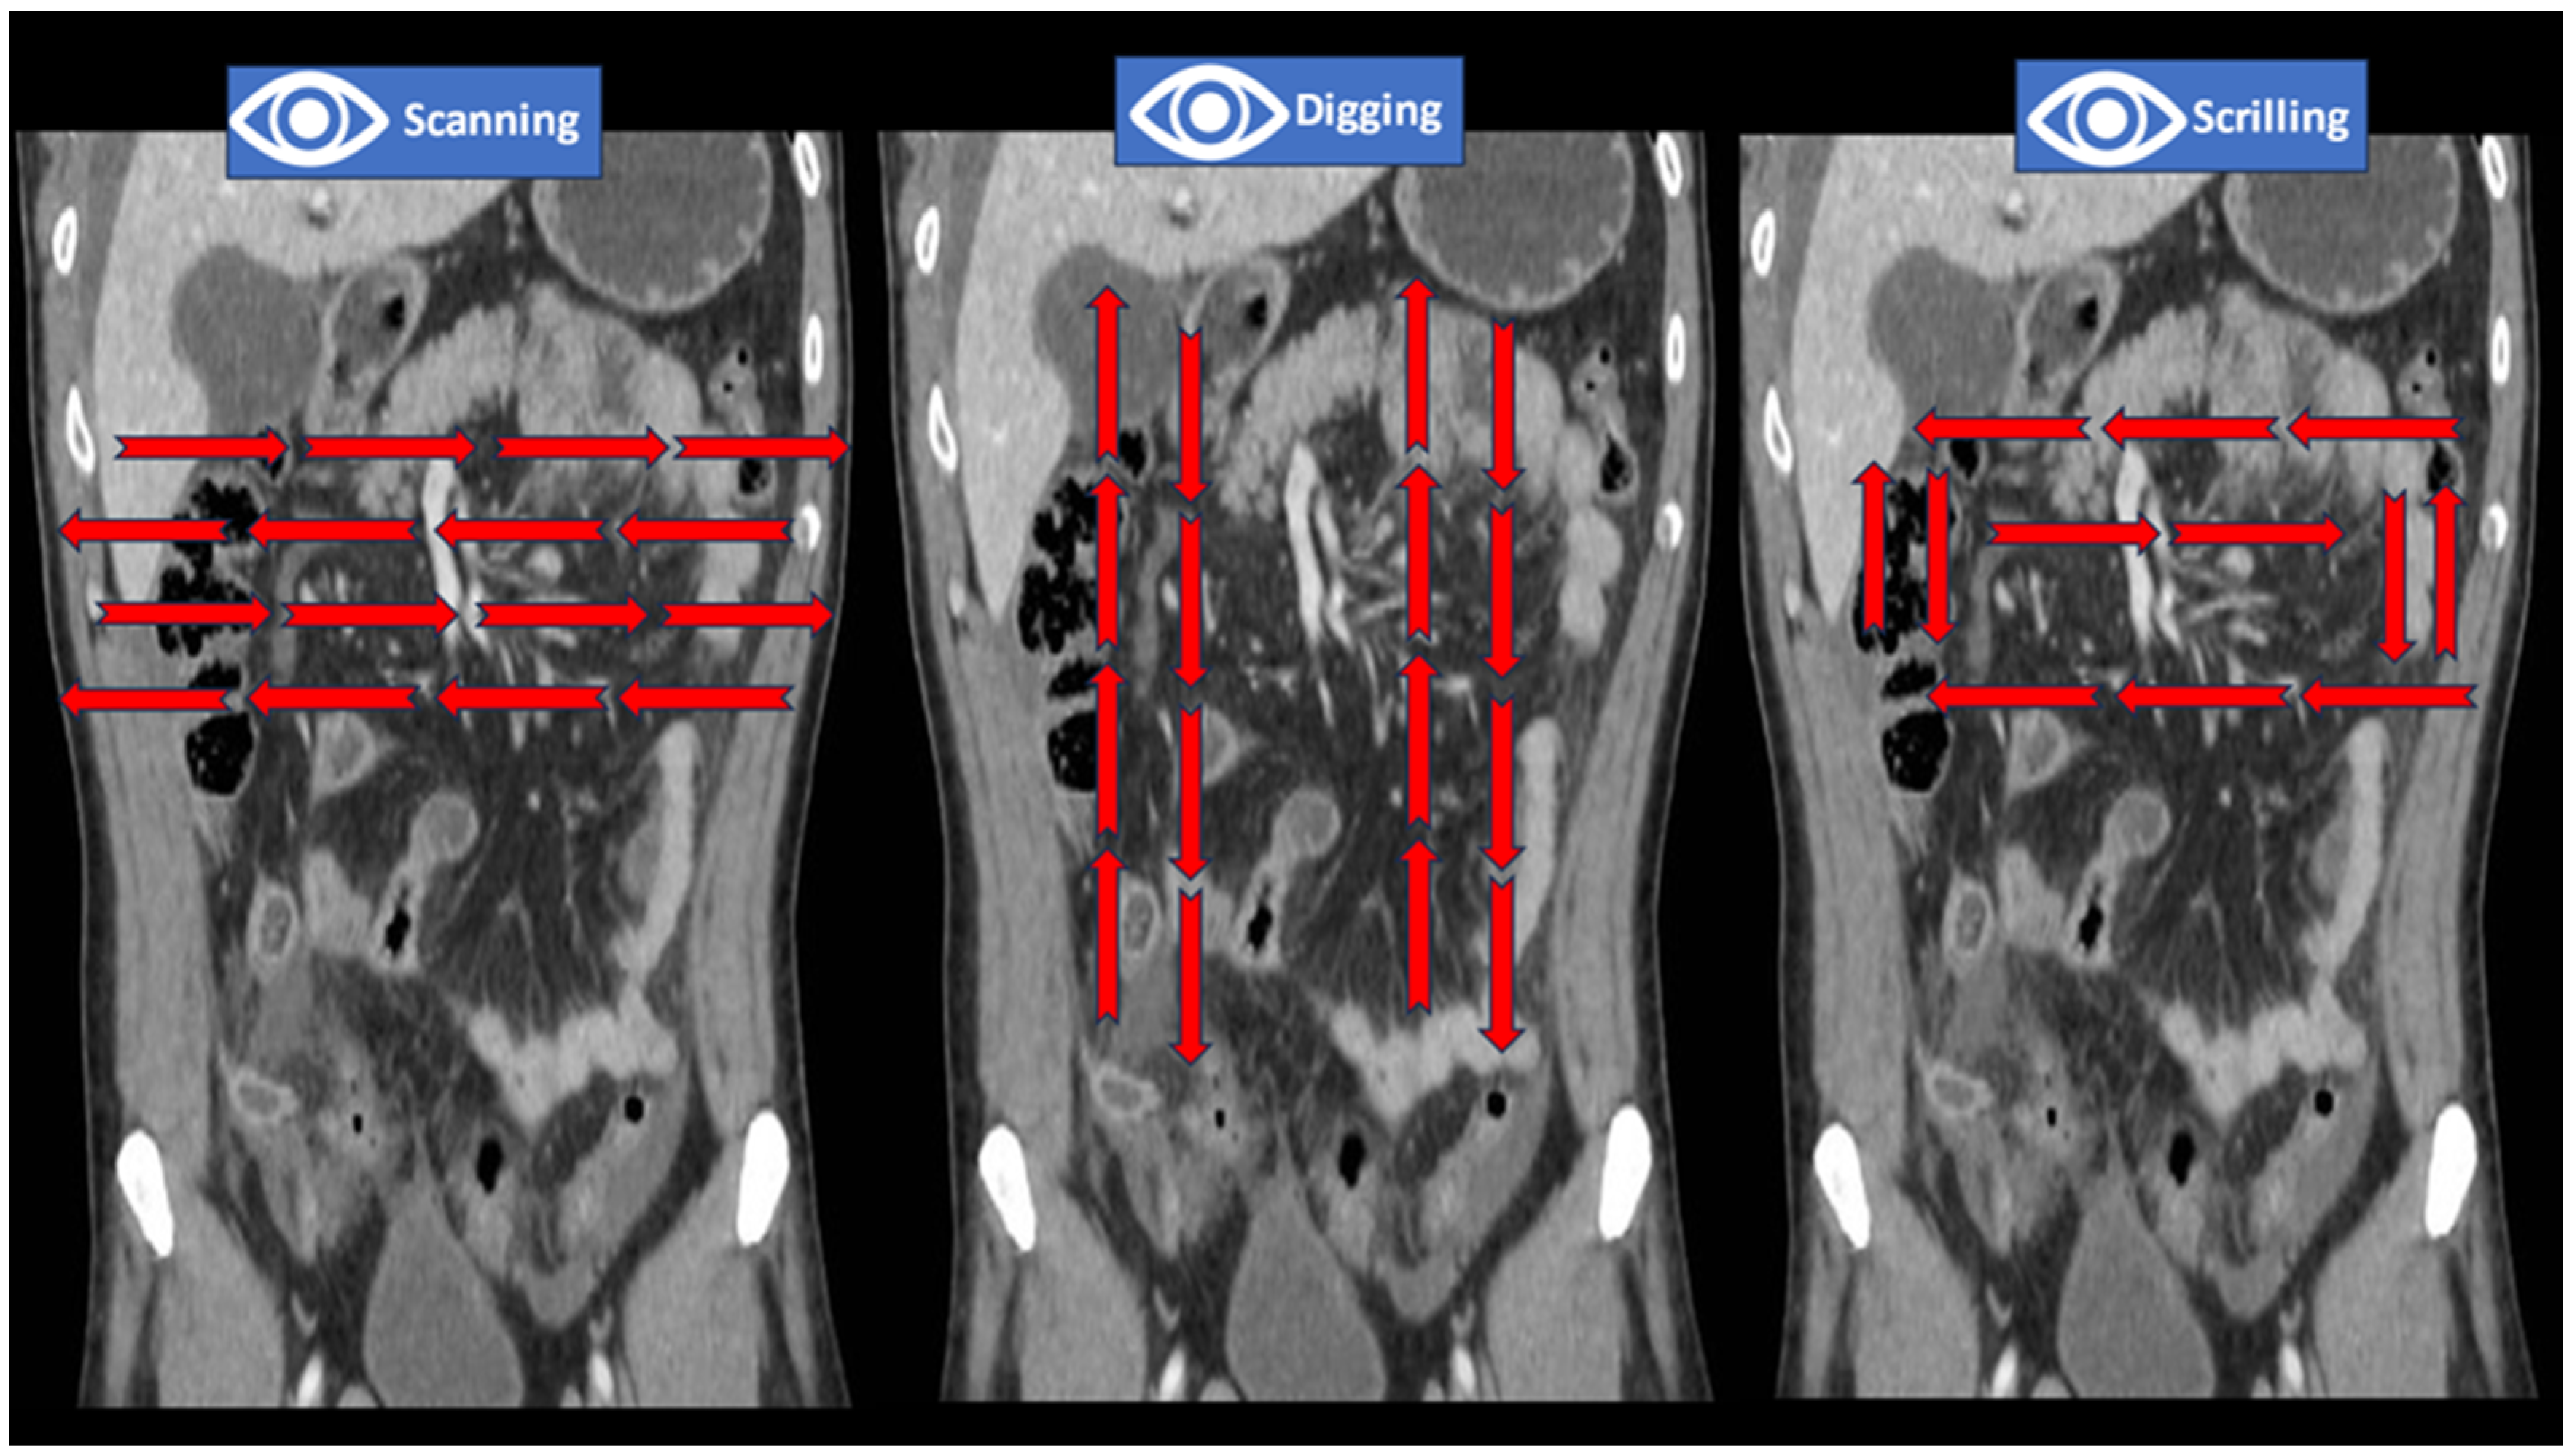

- Drew, T.; Vo, M.L.; Olwal, A.; Jacobson, F.; Seltzer, S.E.; Wolfe, J.M. Scanners and drillers: Characterizing expert visual search through volumetric images. J. Vis. 2013, 13, 3. [Google Scholar] [CrossRef]

- Kliewer, M.A.; Hartung, M.; Green, C.S. The Search Patterns of Abdominal Imaging Subspecialists for Abdominal Computed Tomography: Toward a Foundational Pattern for New Radiology Residents. J. Clin. Imaging Sci. 2021, 11, 1. [Google Scholar] [CrossRef]